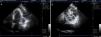

Homem, 58 anos, imunocompetente, antecedentes pessoais de úlcera péptica e hipotensão ortostática. Referenciado para internamento por cardiologista assistente. Tinha iniciado um mês antes dor torácica pleurítica, febre (máximo de 38,5°C), anorexia e derrame pericárdico (12mm). Realizara seis dias de ácido acetilsalicílico (1g 6/6h) por possível pericardite, sem melhoria. Na admissão hospitalar destacavam‐se ainda ortopneia com hipoxemia (pO2=59,5mmHg, em ar ambiente), derrame pleural bilateral (exsudado com predomínio de células linfocitárias), anemia normocitica normocrómica (hemoglobina=11,5g/dL), PCR=19,2mg/dL e VS=120mm/h. O eletrocardiograma evidenciava ritmo sinusal e diminuição difusa da voltagem. Internado para esclarecimento do quadro foi instituída terapêutica de suporte com paracetamol em caso de febre, oxigénio suplementar e cinesioterapia respiratória. Dois dias depois novo ecocardiograma revelou filamentos de fibrina organizados em «teia de aranha» (Figura 1). Foi submetido a pericardiocentese; a biópsia mostrou infiltrado inflamatório e fibrina (Figura 2). As serologias foram positivas para parvovírus B19: IgM=6,04Ua/mL (<1,0) e IgG=4,41Ua/mL (<1,0). As restantes serologias, culturas de sangue, urina e líquido pleural, bem como os marcadores de autoimunidade foram negativos. Teve alta ao 28.° dia de internamento com melhoria completa do quadro clínico, radiológico e analítico. No follow up a três anos, o doente permanece sem sinais de patologia do foro oncológico, infecioso ou autoimune.